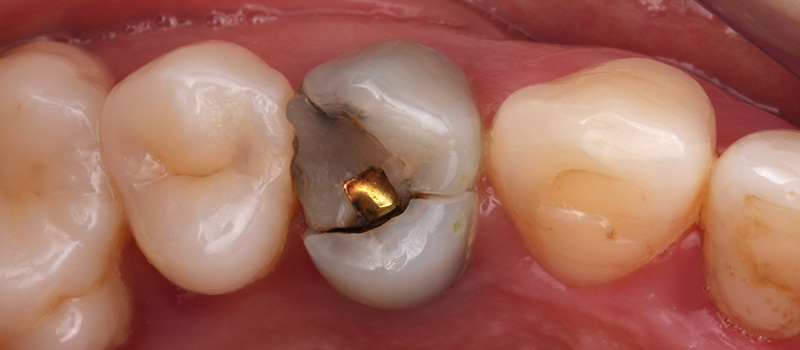

Une patient de 41 ans, consulte au cabinet pour une gêne esthétique et une douleur à la mastication en regard de 14.

Fig. 01 : situation clinique initiale vue vestibulaire, vue latérale et vue occlusale mettant en évidence la fracture du pan palatin de la 14.